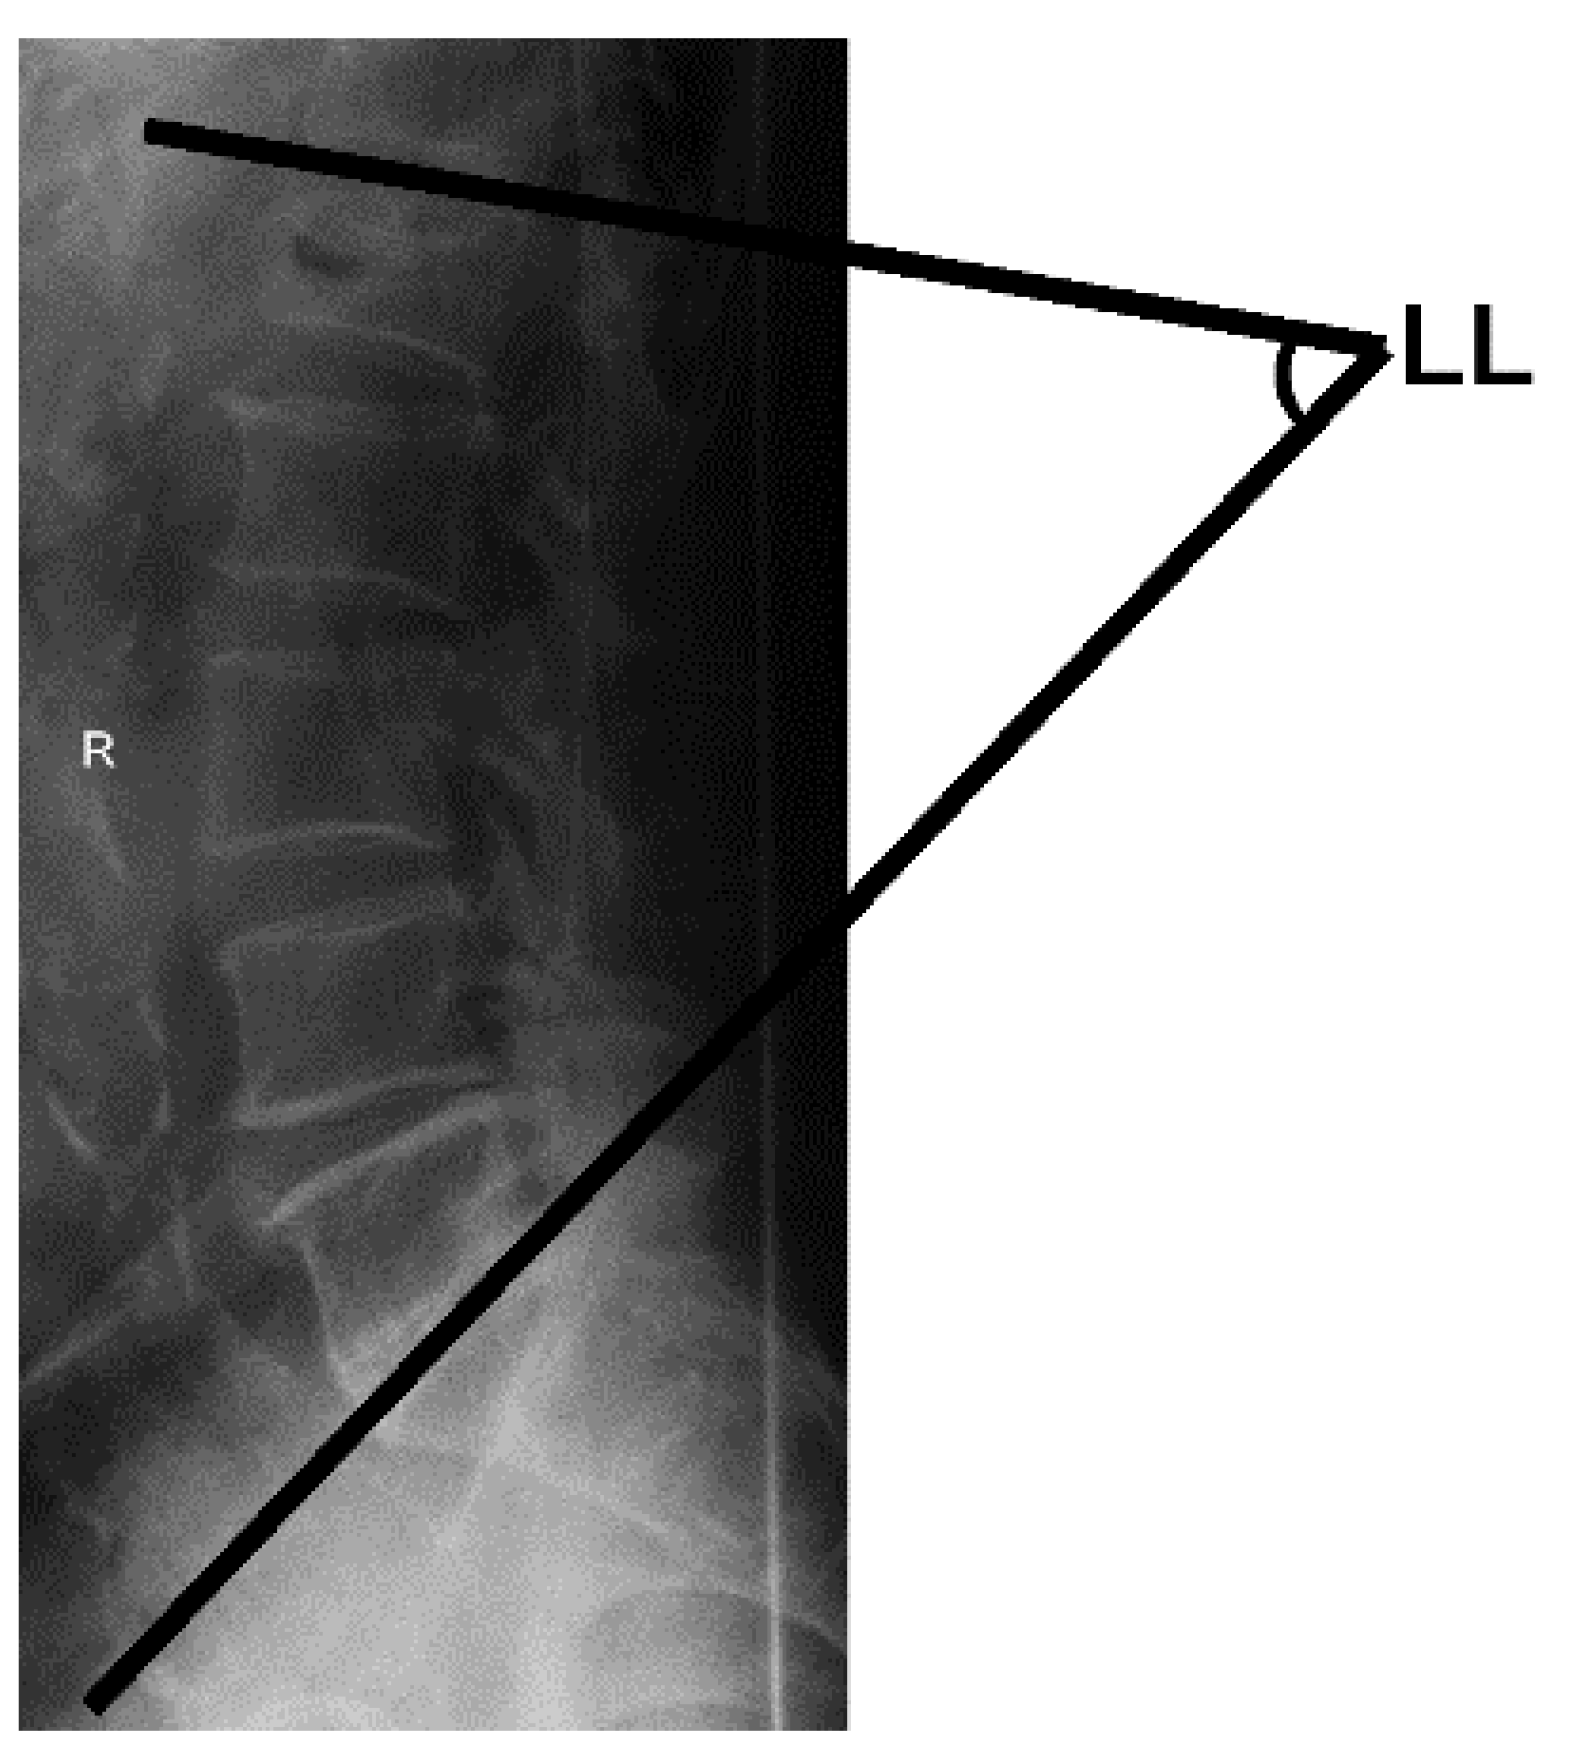

2.2.3. Measurement of the Lumbar Lordosis Angle

To measure the lumbar lordosis angle, each participant was asked to stand with their legs and upper body in a straight line, with their eyes forward and their shoulders flexed at 90°. A lateral radiograph was taken with the cassette at a distance of 1.5 m. The angle between intersecting lines drawn from the upper endplate of the first lumbar vertebra and the upper endplate of the first sacral vertebra comprised the lumbar lordosis angle in the sagittal plane, and the calculated angle determined the severity of curvature, as shown in Figure 4 [31,32,33].

Figure 4.

Total lumbar lordosis (LL) measurement.